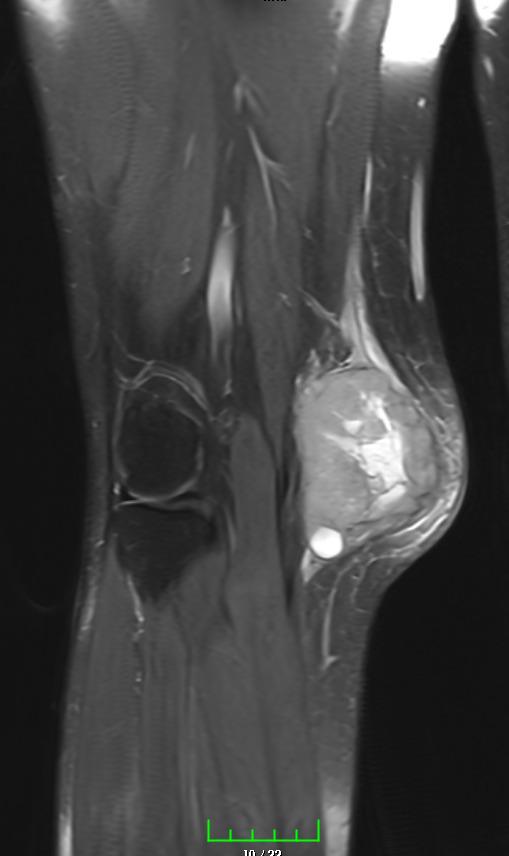

Muscle Cancer